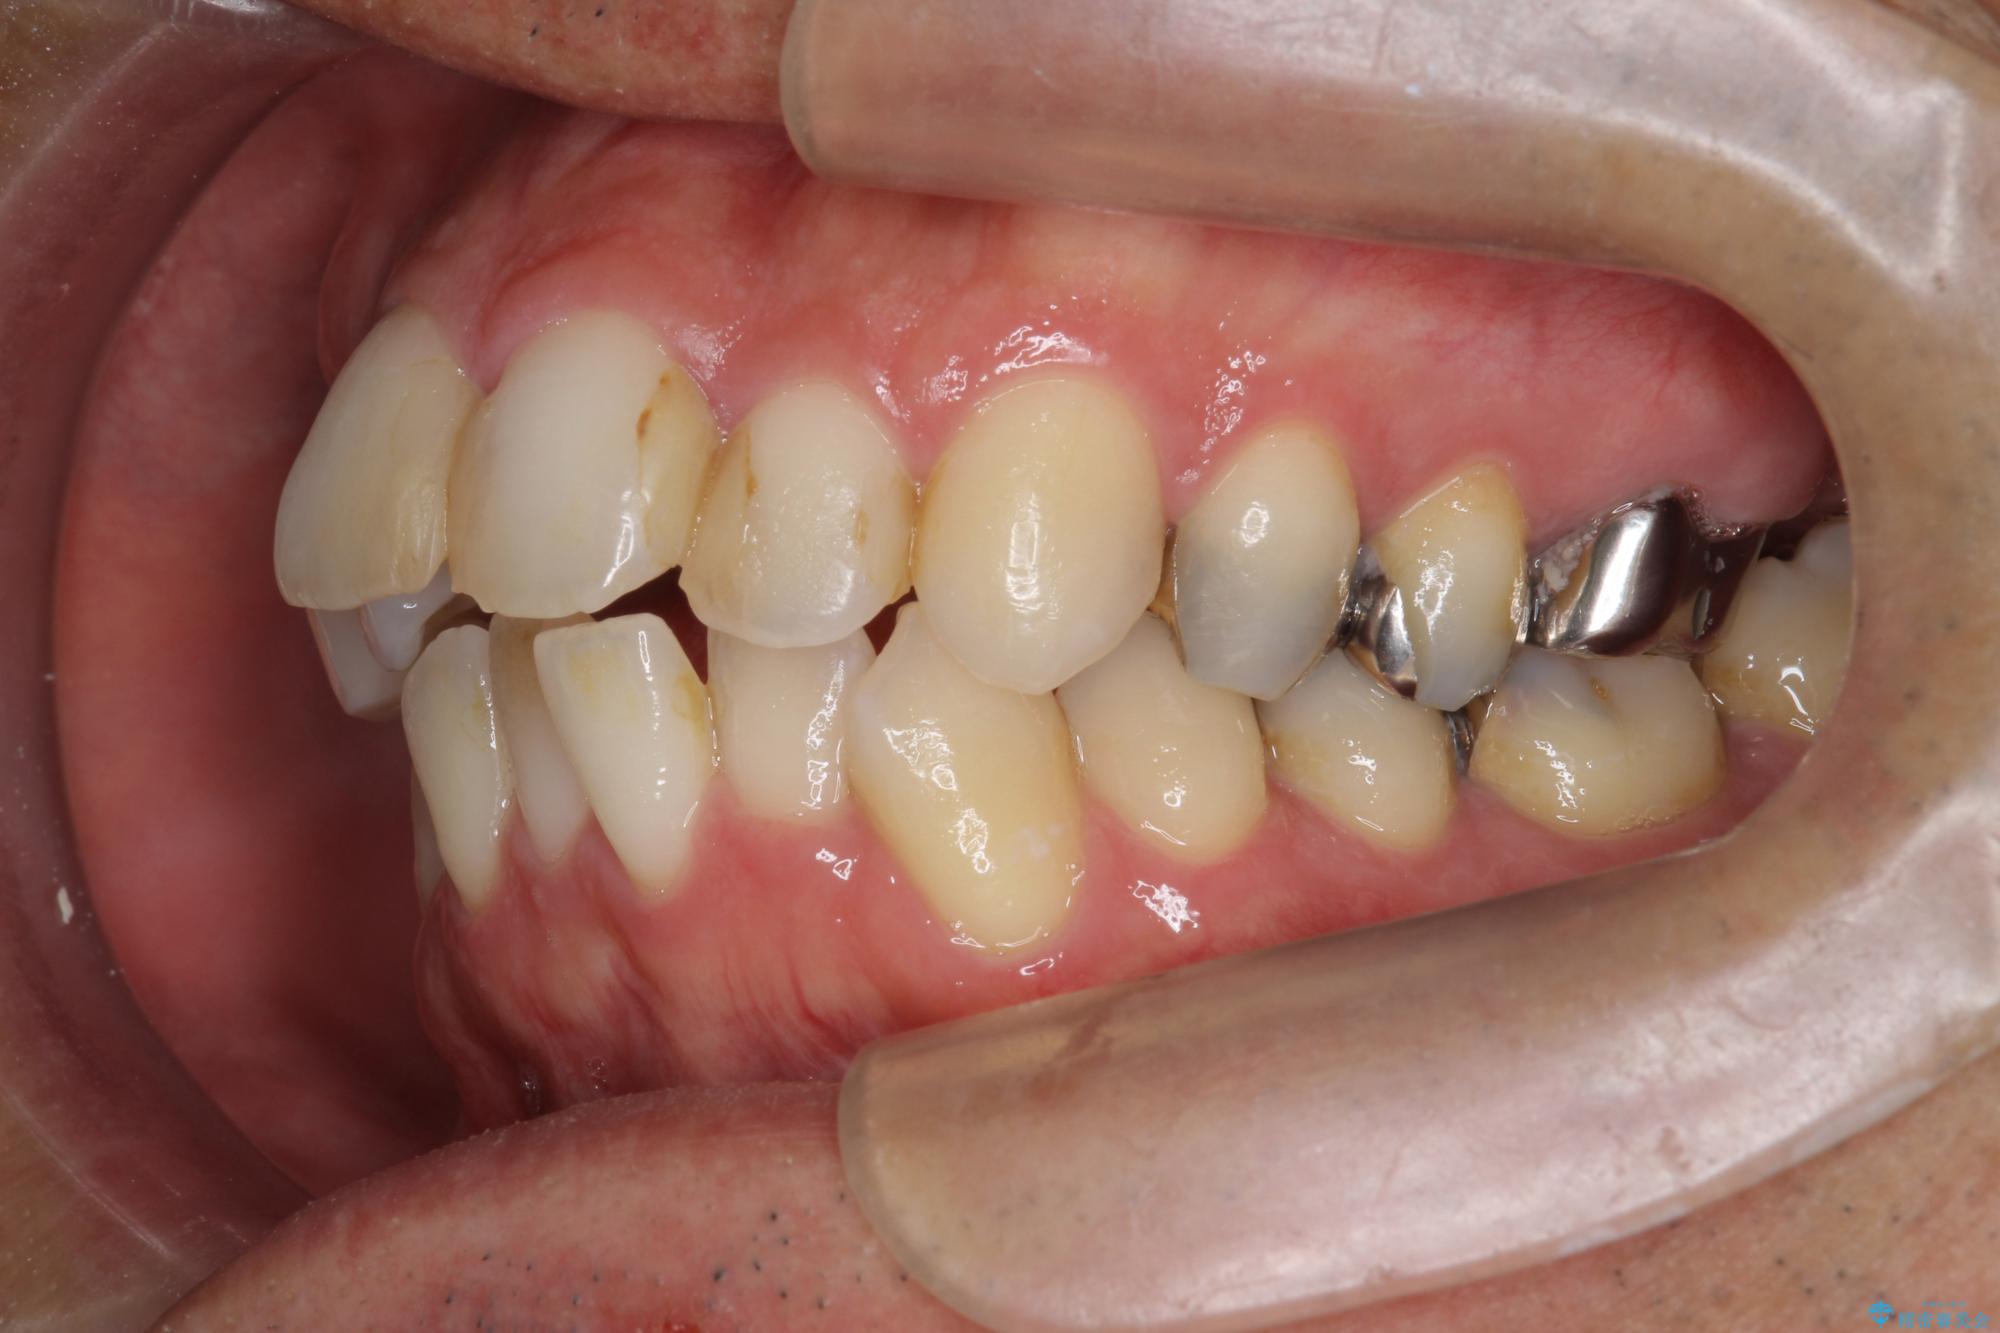

- 突き出た前歯の角度の改善と虫歯治療の改善を求めて来院されました。

虫歯を除去したのち、マウスピース矯正治療を行い、歯並びやがたつきを改善したのち、セラミックに置き換えることで審美性の向上を計画します。